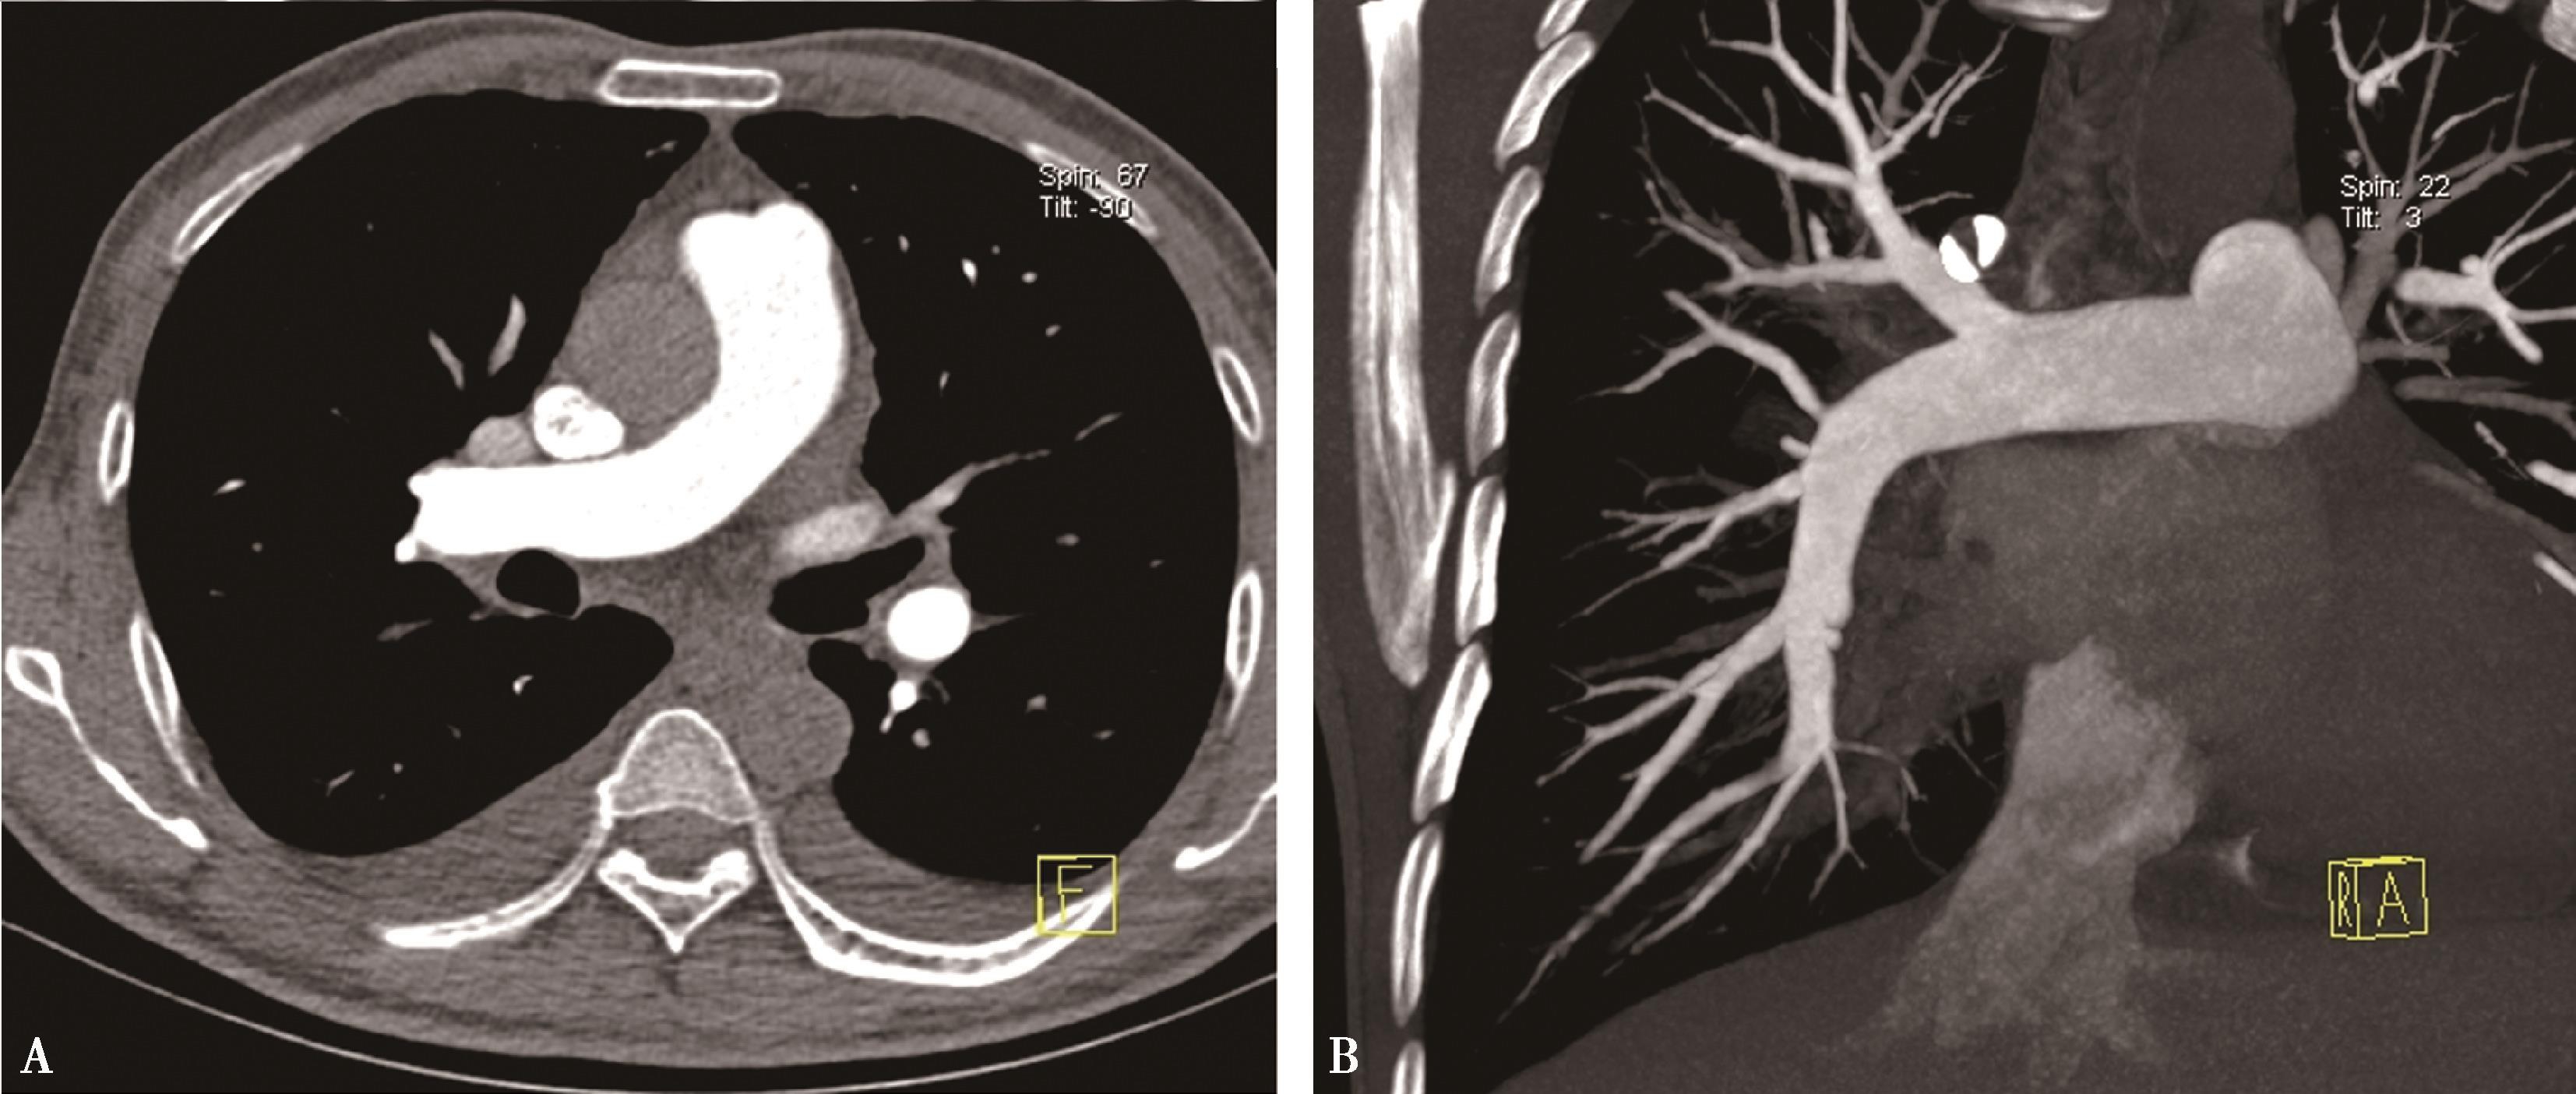

图8-1-4 常规肺动脉CT造影横断图及重建图像

图8-1-5 CTPA两期扫描应用:患者,男,37岁,二尖瓣狭窄,肺循环高压,怀疑肺栓塞。第一期右肺下叶基底段对比剂充盈不充分(ABC↑);第二期充盈充分(DEF↑),排除肺栓塞诊断